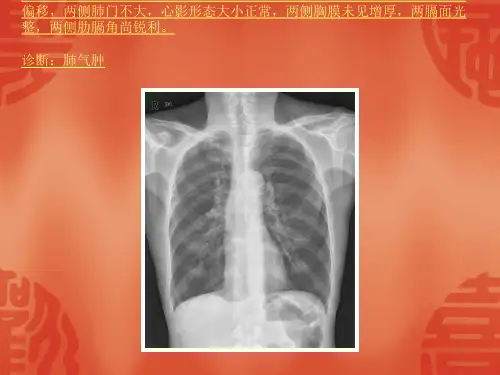

建议大家收藏,方便日后学习哦~肺部肺部病变肺不张(侧位)右上叶肺不张肺部病变肺不张(侧位)右中叶肺不张肺部病变肺不张(侧位)左上叶肺不张肺部病变肺不张(正位)右上叶肺不张肺部病变肺不张(正位)左上叶肺不张肺部病变肺不张左全肺不张肺结核干酪性肺炎肺结核急性粟粒型肺结核肺结核干酪性肺炎肺结核双侧慢性纤维空洞型肺结核肺结核双肺浸润型肺结核肺结核亚性粟粒型肺结核肺结核右上肺结核瘤肺结核右上肺浸润型肺结核肺结核原发型肺结核肺结核左侧慢性纤维空洞型肺结核肺结核原发型肺结核:左胸内淋巴结结核肺气肿、肺心病肺气肿肺气肿、肺心病慢支炎、肺气肺气肿、肺心病慢支炎、肺气肿、肺心病并左侧肺大泡肺气肿、肺心病慢支炎、肺气肿并多发性肺大泡肿、肺心肺气肿、肺心病慢支炎、肺气肿并左下肺感染、右肺大泡肺炎(侧位)右上叶大叶性肺炎肺炎(侧位)右中叶肺脓肿肺炎(侧位)支气管肺炎肺炎(正位)右上叶大叶性肺炎肺炎(正位)右中叶肺脓肿肺炎双下肺支气管扩张肺炎双下肺支气管扩张1肺炎(正位)支气管肺炎肺炎双下肺支气管扩张2肺炎右肺支气管扩张肺炎右肺支气管扩张1肺炎正常支气管造影胸部外伤左第3、4肋骨骨折并左侧创伤性湿肺及少量气胸胸部肿瘤原发性肺癌(侧位)右侧中央型肺癌并右上肺不张(B)胸部肿瘤原发性肺癌(侧位)右上肺周围型肺癌胸部肿瘤原发性肺癌(侧位)右下肺周围型肺癌胸部肿瘤原发性肺癌(侧位)左侧中央型肺癌胸部肿瘤原发性肺癌(高KV点胸部肿瘤原发性肺癌(正位)右侧中央型肺癌并右上肺不张(A)胸部肿瘤原发性肺癌(正位)右上肺周围型肺癌片)左侧中央型肺癌并左肺全肺不张(B)胸部肿瘤原发性肺癌(正位)右下肺周围型肺癌胸部肿瘤原发性肺癌(正位)左侧中央型肺癌(A)胸部肿瘤原发性肺癌(正位)左侧中央型肺癌胸部肿瘤原发性肺癌(正位)左侧中央型肺癌并左肺全肺不张(A)胸部肿瘤原发性肺癌肋骨内生性软骨瘤,勿误以为周围性肺癌(B)胸膜病变胸膜钙化左侧胸膜钙化胸膜病变胸膜钙化左侧胸膜增厚、钙化骨科骨关节感染关节强直髋关节骨性强直骨关节感染化脓性关节炎化脓性关节炎佝偻病骨关节感染化脓性关节炎右第二掌骨-食指近节骨化脓性关节炎骨关节感染急性化脓性骨髓炎急性化脓性骨髓炎骨关节感染急性化脓性骨髓炎急性化脓性骨髓炎1骨关节感染慢性骨脓肿慢性骨脓肿骨关节感染慢性骨脓肿慢性骨脓肿1骨关节感染慢性骨脓肿慢性骨脓肿2骨关节感染慢性化脓性骨髓炎慢性化脓性骨髓炎骨关节感染慢性化脓性骨髓炎慢性化脓性骨髓炎1骨关节感染慢性化脓性骨髓炎慢性化脓性骨髓炎2骨关节结核干骺端结核骨关节结核骨骺及干骺端结核骨关节结核膝关节结核骨关节结核右拇指近节指骨、左骨关节结核胸椎结核并冷脓肿形成第五掌骨结核骨关节外伤骨折 Colle's骨折骨关节外伤骨折胫骨下段斜形骨折骨关节外伤骨折螺旋形骨折骨关节外伤骨折拇指粉碎性骨折骨关节外伤骨折桡骨下端骺离骨折骨关节外伤骨折桡骨下段青枝骨折骨关节外伤骨折嵌入性骨折骨关节外伤关节脱位创伤性关节炎骨关节外伤关节脱位腓骨下段螺旋形骨折并踝关节半脱位骨关节外伤骨折斜形骨折骨关节外伤关节脱位骨折畸形愈合骨关节外伤关节脱位肩关节完全性脱位骨关节外伤关节脱位尾指近中节骨粉碎性骨折并完全性脱位骨关节外伤关节脱位肘关节完全性脱位骨肿瘤良性骨肿瘤(侧位)骨软骨瘤骨肿瘤良性骨肿瘤(正位)骨软骨瘤骨肿瘤良性骨肿瘤多发性内生性软骨瘤骨肿瘤良性骨肿瘤肱骨上段骨囊肿并病理性骨折骨肿瘤良性骨肿瘤骨软骨瘤骨肿瘤良性骨肿瘤胫骨下段骨囊肿骨肿瘤良性骨肿瘤巨细胞瘤骨肿瘤良性骨肿瘤巨细胞瘤1骨肿瘤良性骨肿瘤巨细胞瘤恶变骨肿瘤良性骨肿瘤内生性软骨瘤其它骨关节疾病类风湿性关节炎类风湿性关节炎其它骨关节疾病强直性脊柱炎强直性脊柱炎其它骨关节疾病强直性脊柱炎强直性脊柱炎1其它骨关节疾病强直性脊柱炎强直性脊柱炎2其它骨关节疾病退行性骨关节病颈椎退行性改变其它骨关节疾病退行性骨关节病膝关节退行性改变正常骨关节表现常成人表现正常骨关节表现正常脊柱、骨盆正常骨关节表现正常成人表现骨正常骨关节表现正常小儿表现正常骨关节表现正常小儿表现1心血管风湿性心脏病:二尖瓣狭窄风湿性心脏病二尖瓣狭窄(后前位)风湿性心脏病:二尖瓣狭窄风湿性心脏病二尖瓣狭窄(左侧位)风湿性心脏病:二尖瓣狭窄并关闭不全风湿性心脏病二尖瓣狭窄并关闭不全(后前位)风湿性心脏病:二尖瓣狭窄并关闭不全风湿性心脏病二尖瓣狭窄并关闭不全(左侧位)后天性心脏病肺源性心脏病慢支炎、肺气肿、肺心病后天性心脏病肺源性心脏病慢支炎、肺气肿、肺心病并左上肺大泡后天性心脏病高血压性心脏病高血压性心脏病后天性心脏病心包病变大量心包积后天性心脏病心包病变缩窄性心包炎(后前位)后天性心脏病心包病变缩窄性心包炎(左侧位)后天性心脏病心肌病心肌病(后前位)后天性心脏病心肌病心肌病(左侧位)基本病变肺血减少基本病变肺郁血基本病变急性肺水肿(床边卧位片)基本病变间质性肺水肿基本病变普大型心脏基本病变右心房增大基本病变 右心室增大 基本病变 右心室增大1基本病变 右心室增大2基本病变 左心房增大、左主支气管上抬基本病变 右心室增大3基本病变 左心房增大基本病变 左心房增大1基本病变 左心房增大2基本病变 左心室增大正常表现正常心脏后前基本病变左心室增大1正常表现心脏大血管与心脏关系侧位片正常表现正常心脏右前侧位片正常表现正常心脏左侧位片正常表现正常心脏左前侧位片泌尿结核腹腔淋巴结钙化结核膀胱结核:挛缩膀胱结核右肾、膀胱结核,左侧代偿性扩张结核右肾、输尿管结核结核右肾上盏结核:脓肿形成结核左侧肾结核:肾自截(A)结核左侧肾结核:肾自截(B)结核左肾结核(A)结核左肾结核(B)结核左肾结核(C)结石膀胱阳性结石(B)结石胆囊阳性结石(A)结石胆囊阳性结石(B)结石胆囊阳性结石(C)结石多发性膀胱阴性结石结石膀胱阳性结石(A)结石尿道结石结石双肾铸型结石结石左输尿管下段结石、右输尿管上段结石(A)结石左输尿管下段结石、右输尿管上段结石(B)泌尿系肿瘤膀胱癌膀胱癌泌尿系肿瘤膀胱癌右侧壁膀胱癌泌尿系肿瘤肾癌右肾癌泌尿系肿瘤肾癌右肾癌泌尿系肿瘤肾盂癌右肾盂癌伴输尿管种植转移泌尿系肿瘤肾癌右肾癌1泌尿系肿瘤肾盂癌左肾盂癌前列腺肥大消化急腹症肠梗阻 (立位)小肠低位性机械性肠梗阻(B)急腹症肠梗阻 (立位)小肠低位性机械性肠梗阻急腹症肠梗阻绞窄性肠梗阻急腹症肠梗阻麻痹性肠梗阻急腹症肠套叠肠套叠空气灌肠复位成功(B)急腹症肠梗阻绞窄性肠梗阻1急腹症肠套叠肠套叠空气灌肠复位过程(A)急腹症胃、肠扭转乙状结肠扭转(A)急腹症胃、肠扭转乙状结肠扭转(B)急腹症消化道穿孔 (侧卧体水平投照)消化道穿孔:腹腔游离气体急腹症消化道穿孔消化道穿孔:双膈下游离气体急腹症消化道金属异物胃内金属异物结核肠结核(溃疡型)1结核肠结核(溃疡型)结核肠结核(增生型)结石 (ERCP造影):总胆管下端阴性结石结石胆囊多发性阴性结石(A)结核腹腔淋巴结钙化结石胆囊及胆囊管阴性结石。